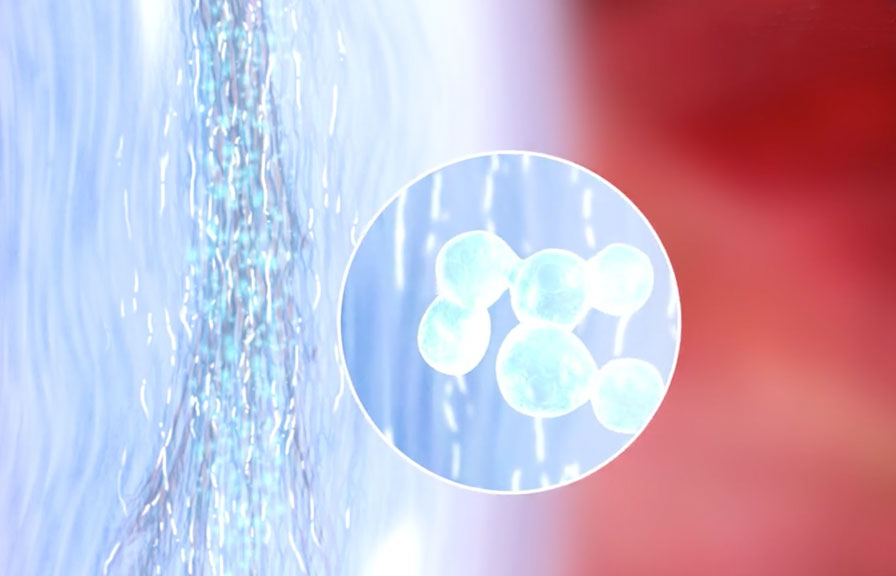

Have you had a back or neck surgery? Do you still have pain? If you suffer from chronic pain due to:

- Failed back surgery

- Arthritis

- Fibromyalgia

- Pain after surgery

- Spinal Stenosis

- Pinched Nerves

- Sciatica

- Cancer

- Diabetic neuropathy